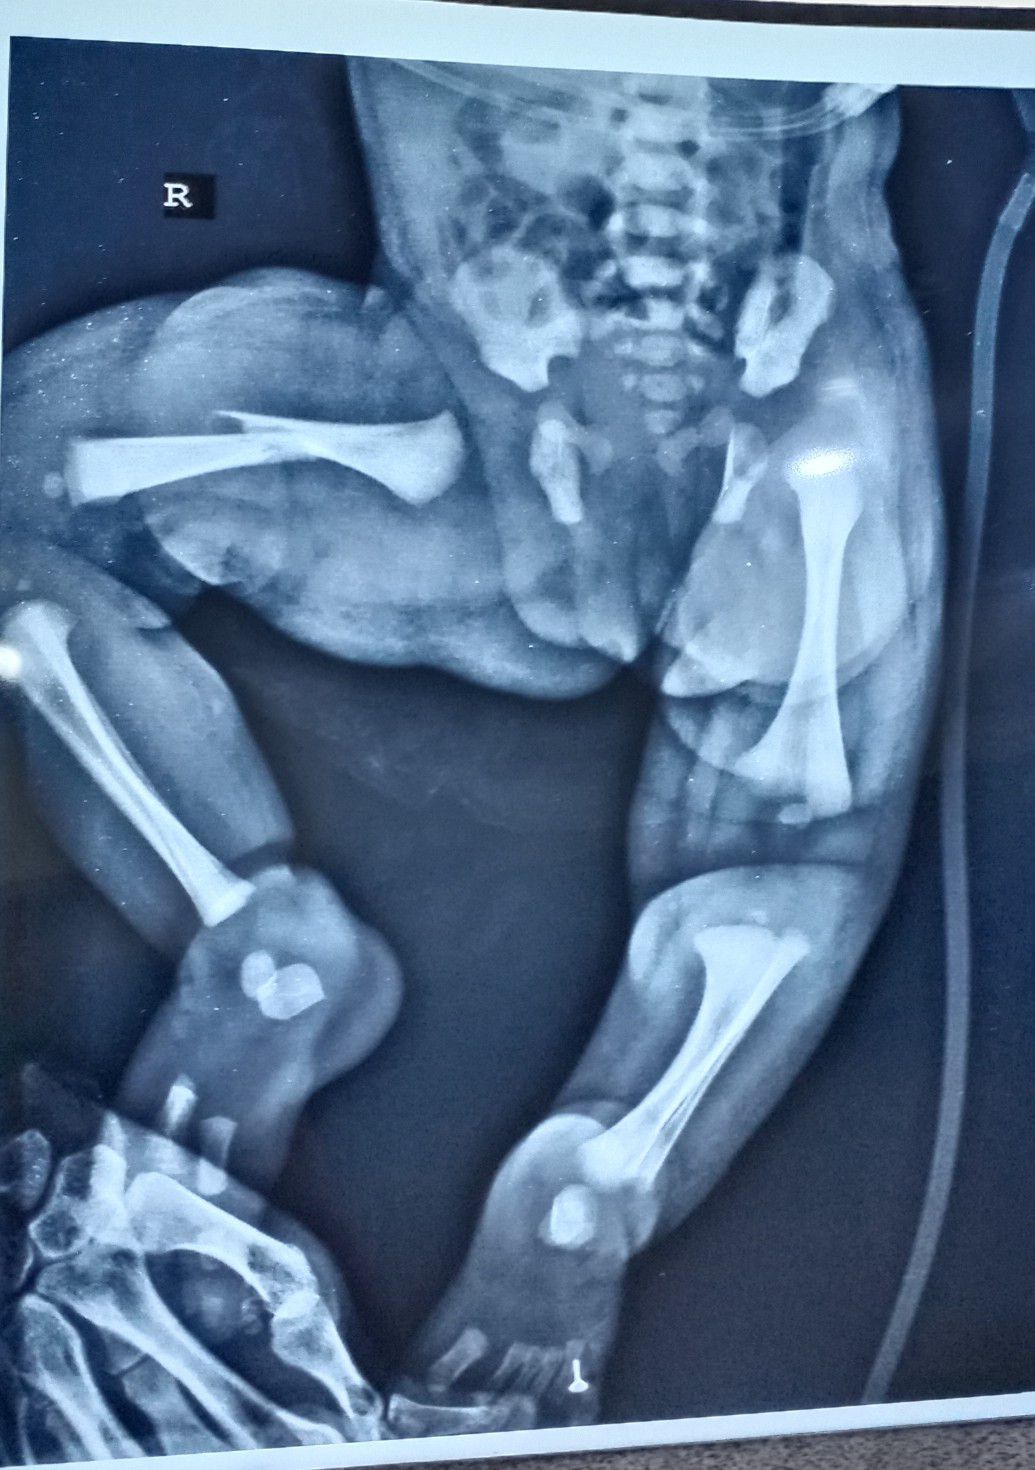

Femur fracture

Femur fracture in new born during delivery.

Fracture

Labour

Femurfracture

Obstructed Labour